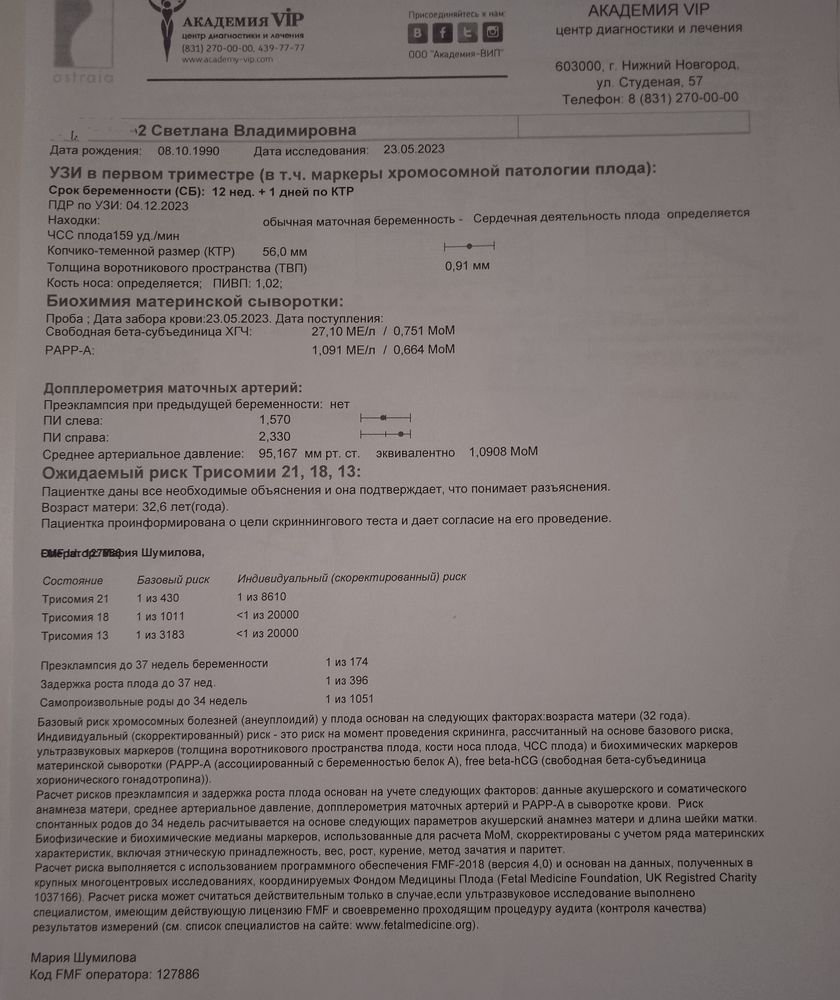

К этому врачу на это время уже пришли пациенты... Начали разбираться а меня записали не на 23 мая а на 23 июня🥴Муж после операции на колено, рулил такое расстояние, я думала нас отправят ни с чем.. Но предложили осмотр у другого врача, кмн,стаж 36 лет, я конечно расстроилась но согласилась. Василёк наш тоже видимо был не настроен показывать себя как надо и как бы мы не старались, что бы мы не делали, в профиль он не лёг, кувыркался швырялся но в профиль нет, в итоге кость носа осматривали с лица, складку(твп) вообще не знаю с какой стороны, зато торчок показал во всей красе 🙈врач сказала если не отпадёт мальчик будет 🤞🙌тут конечно я расплылась.... Появилась надежда что наша мечта о сынуле всё таки осуществится🙏Я с 9 утра до сдачи крови в 5 вечера была голодная(ещё и с ночной смены на ногах не спамши🤪),кровь сдала, попросила горячего чая, пока ждали заключения, всё хорошо, риски низкие, фото в этот раз мы красивые не получили, Василёк и там не поддался🤪А сегодня в городе я прошла скрининг по омс, на УЗИ меня опять крутили вертели, ну не хочет дитя что бы его разглядывали, вроде тоже всё хорошо, правда кровь недели через 2 с рисками, но я уже особо не жду, но пусть будет. Врач в конце, пол могу сказать если хочешь узнать, я говорю там торчок☺она говорит да, там мальчик 🙏Я пока сильно не обольщаюсь, но очень хочу что бы у нас и не отпало и не рассосалось ничего и моё материнское сердце немного залечит наш маленький сынок о котором мы с папой так мечтаем🙏🙏🙏но главное что бы живыми здоровыми и в срок 🙏💫

Ксю, вот результат в жц и пометки врача что в норме а что нет🙂кровь норма

Ксю, вот результат в жц и пометки врача что в норме а что нет🙂кровь норма